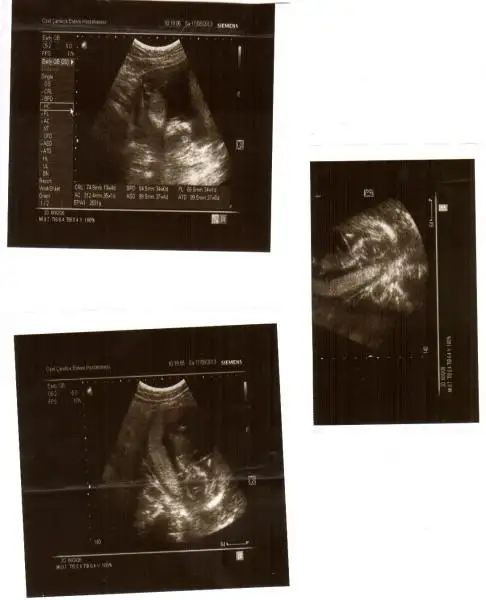

Eki Görüntüle 776535

kızlar benim resimlerede bi yorum yapın ne acaba?ben anlayamadım.çabuk yazın çok merak ediyorum![]()

hayret bu resme gore kiz dr erkek demis gerci resim tamda net degil allhim tamamina erdirsin